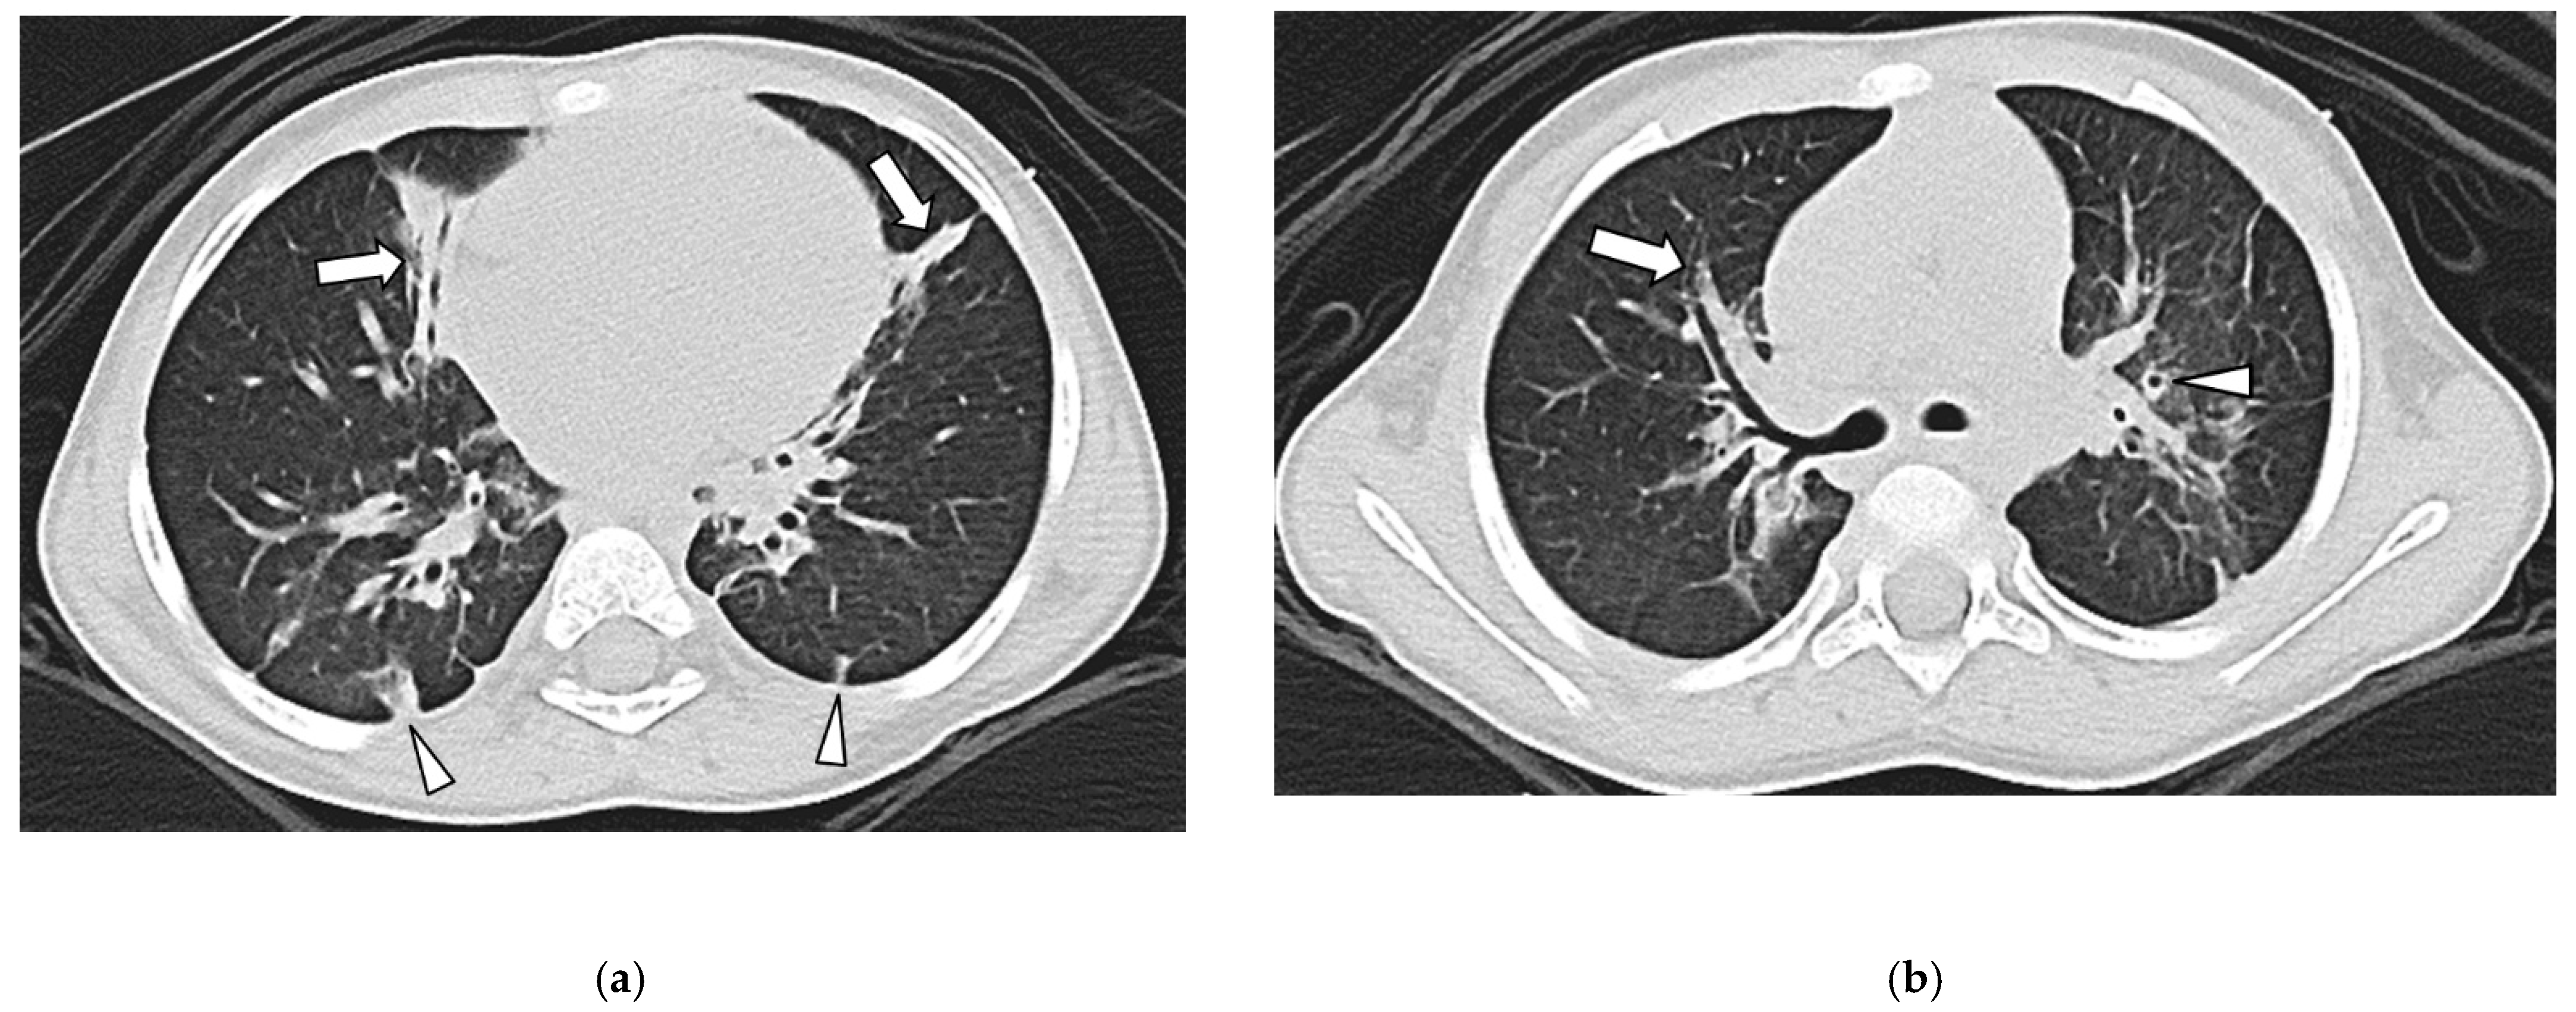

3.2. Thoracic MDCT Findings

3.3. Lung Findings

3.4. Airway Findings

3.5. Pleural Findings

3.6. Interobserver Agreement

| Septal Thickening | 39/49 (76%) | 0/54 (0%) | <0.001 |

| Bronchial Wall Thickening | 0/49 (0%) | 33/54 (61%) | <0.001 |

| Bronchiectasis | 0/49 (0%) | 30/54 (56%) | <0.001 |

| Pleural Thickening | 44/49 (90%) | 2/54 (4%) | <0.001 |